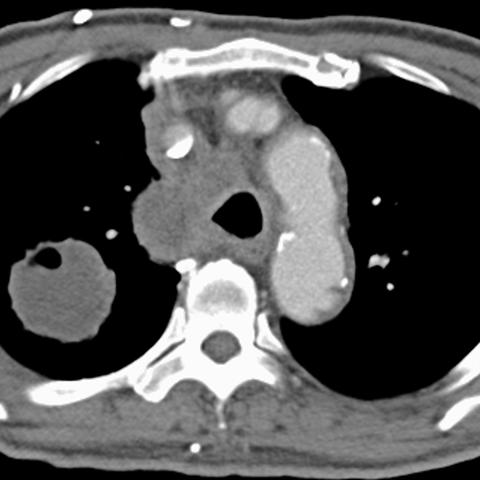

Mediastinal Lymphadenopathy, Lung Cancer (Chest CT) [2 of 3]